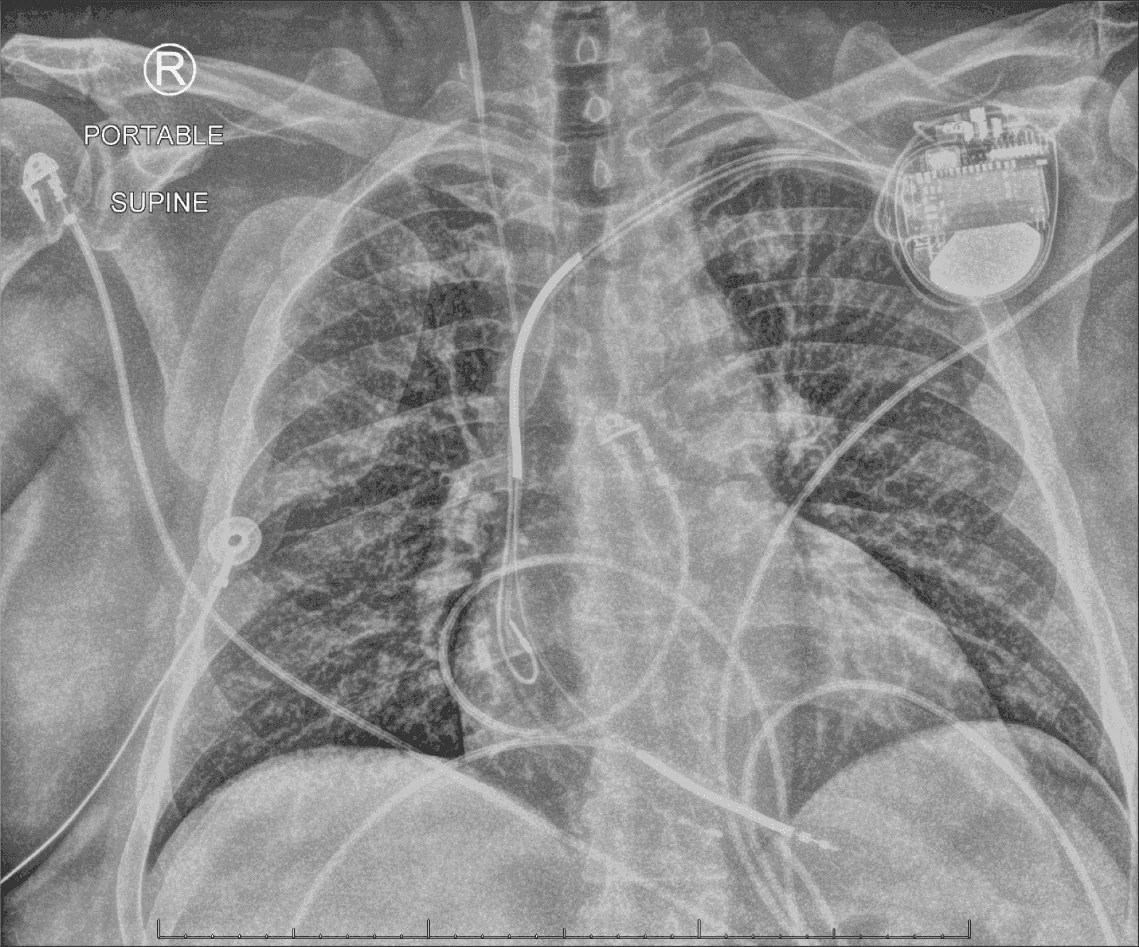

From www.researchgate.net

Chest Xray of a male patient after SICD implantation. The generator... Download Scientific Pain In Left Arm After Icd Implant This is not uncommon for icd recipients, especially in the first months or year. Some of the risks that may be encountered during the implant procedure include the following: Shoulder pain and disability ipsilateral to the implant site is a common complication of cardiac rhythm device implantation, yet very little has been published about this. Formation of a blood clot;. Pain In Left Arm After Icd Implant.